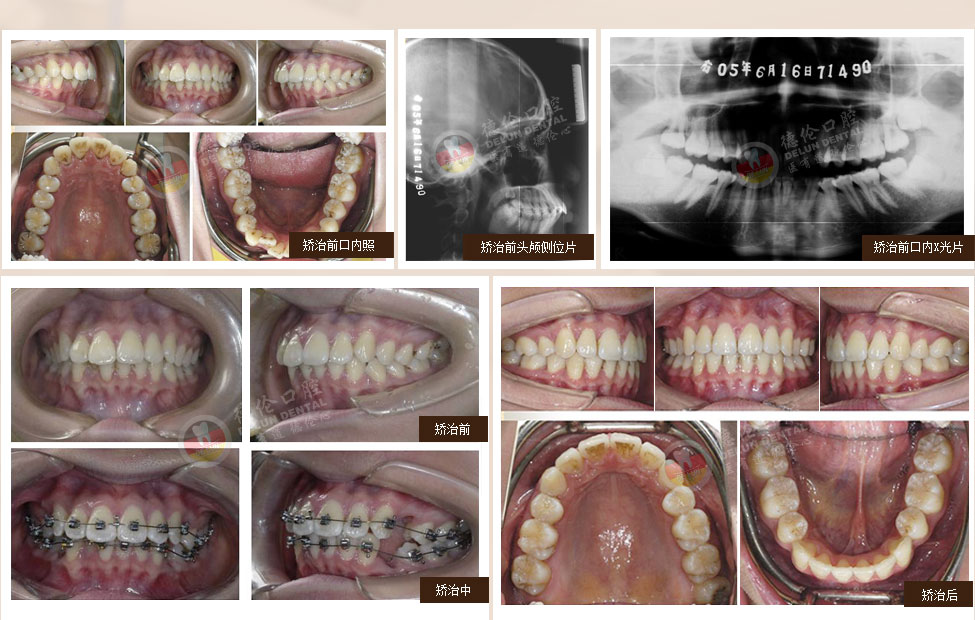

• 女:13歲

癥狀:上下前牙前突、唇傾,上下牙弓散在間隙

矯治方法:SPEED矯治器結(jié)合種植釘、整體內(nèi)收上下牙弓、改善雙牙弓前突以及凸面型側(cè)貌

• 男:17歲

癥狀:下頜右側(cè)第二、第三磨牙水平阻生,下頜左側(cè)第三磨牙水平阻生

矯治方法:下頜拔除兩顆第三磨牙(智慧齒)

• 女:19歲

癥狀:上下前牙前突(雙牙弓前突)

矯治方法:SPEED自鎖矯治器治療 拔除上下第一雙尖牙、排齊上下牙列、內(nèi)收上下牙弓,改善面部側(cè)貌。

• 女:24歲

癥狀:牙列不齊、下頜第二、第三磨牙水平阻生,左側(cè)磨牙鎖牙合

矯治方法:拔除上頜及右下第一雙尖牙,左下第二雙尖牙以及2個下第三磨牙